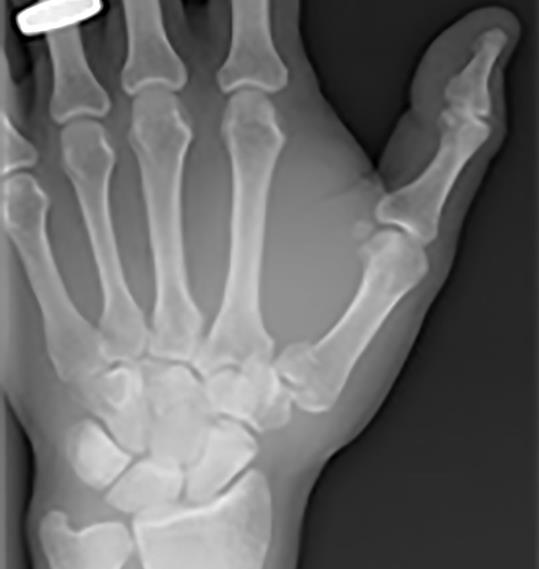

A 33-year-old woman sustained an injury to her thumb when she awkwardly caught a ball.

Which of the following is the most appropriate action?

A. Thumb spica splint

B. Advices only

C. Immediate manipulation in ED

D. Refer to fracture clinic

E. Refer for internal fixation